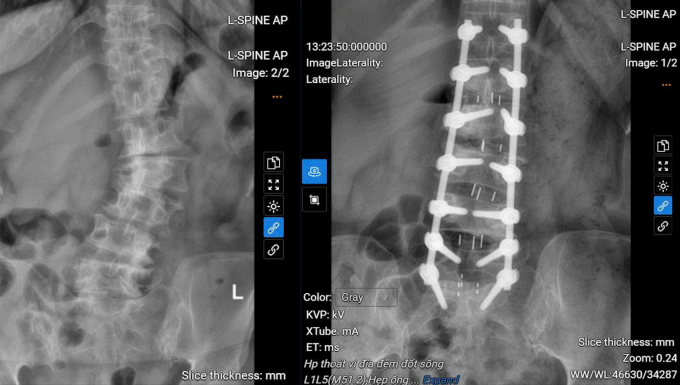

Bác sĩ Duận loại bỏ các cấu trúc gây chèn ép và mở rộng ống sống, từ đó tạo khoảng không gian để giải phóng tủy và các rễ thần kinh. Tiếp theo, các phần đĩa đệm thoát vị, gai xương... được loại bỏ và thay đĩa đệm để hàn khớp liên thân đốt sống đảm độ vững của cột sống. Cuối cùng, bác sĩ bắt vít cố định và nắn chỉnh lại cột sống của người bệnh.

Hệ thống C-arm hỗ trợ bác sĩ định vị chính xác vị trí bắt vít, giảm nguy cơ tổn thương thần kinh, rút ngắn thời gian phẫu thuật. Nhờ đó, giảm nguy cơ mất máu và hạn chế xâm lấn, người bệnh phục hồi nhanh hơn. Ca phẫu thuật kéo dài 5 giờ, 14 vít được sử dụng.